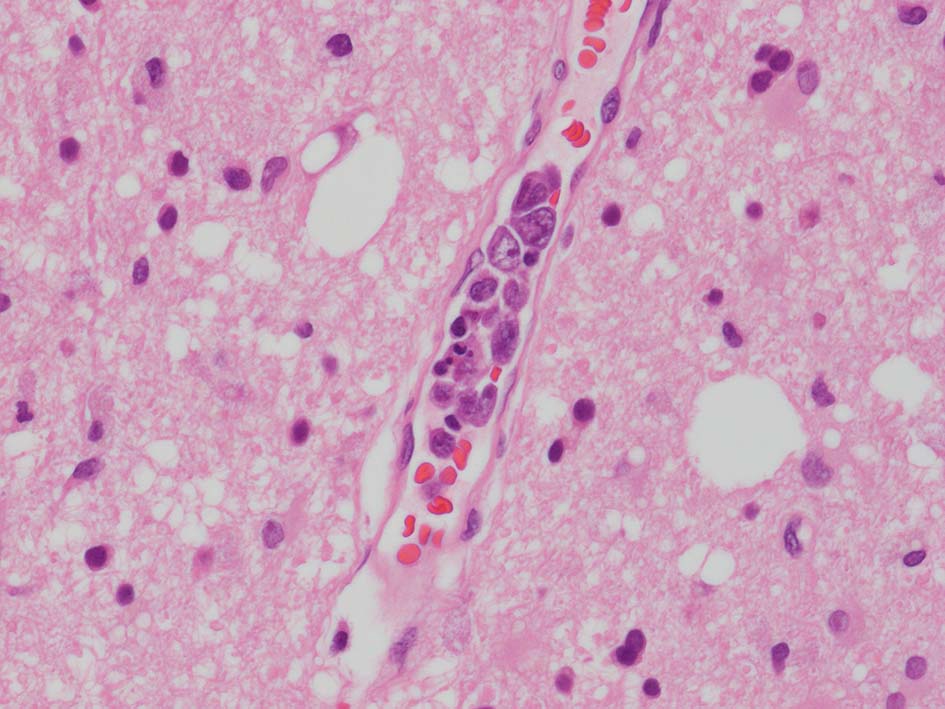

脳梗塞病変の脳生検組織

梗塞組織近傍の細血管内に腫瘍細胞が認められる.